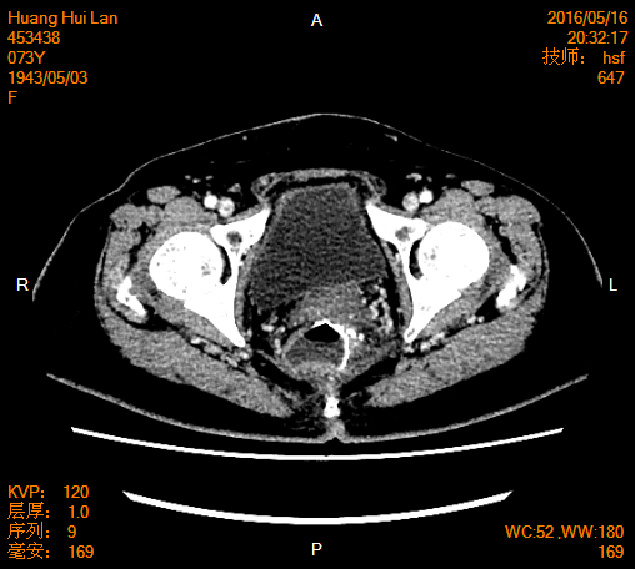

2016-04-13胸腹盆CT

左侧附件区肿块,代谢活跃,考虑卵巢囊腺癌;直肠壁增厚,代谢活跃,考虑直肠癌并周围淋巴结转移可能性大,建议肠镜检查;双肺多发结节,考虑转移瘤;腹腔积液

2016-05-17胸腹盆CT(术后基线)